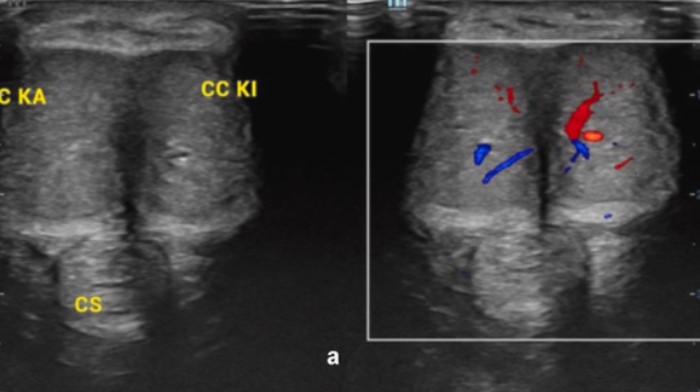

Kemudian mengacu pada pemeriksaan fisik, dokter menemukan ereksi pada batang penis disertai kelemahan pada kelenjar penis. Diagnosis klinis pasien adalah priapisme non-iskemik. Dokter bedah awal mencoba mengalirkan darah dari penisnya sebagai upaya meringankan ereksi. Akan tetapi usaha percobaan tersebut tak membuahkan hasil.

Dokter kemudian memasang pintasan untuk membantu aliran darah di penis. Setelah beberapa pemeriksaan lebih lanjut, dokter menemukan kanker telah menyebar ke penisnya. Dokter pun memutuskan untuk mengamputasi penis pria tersebut untuk menghentikan penyebaran penyakit.